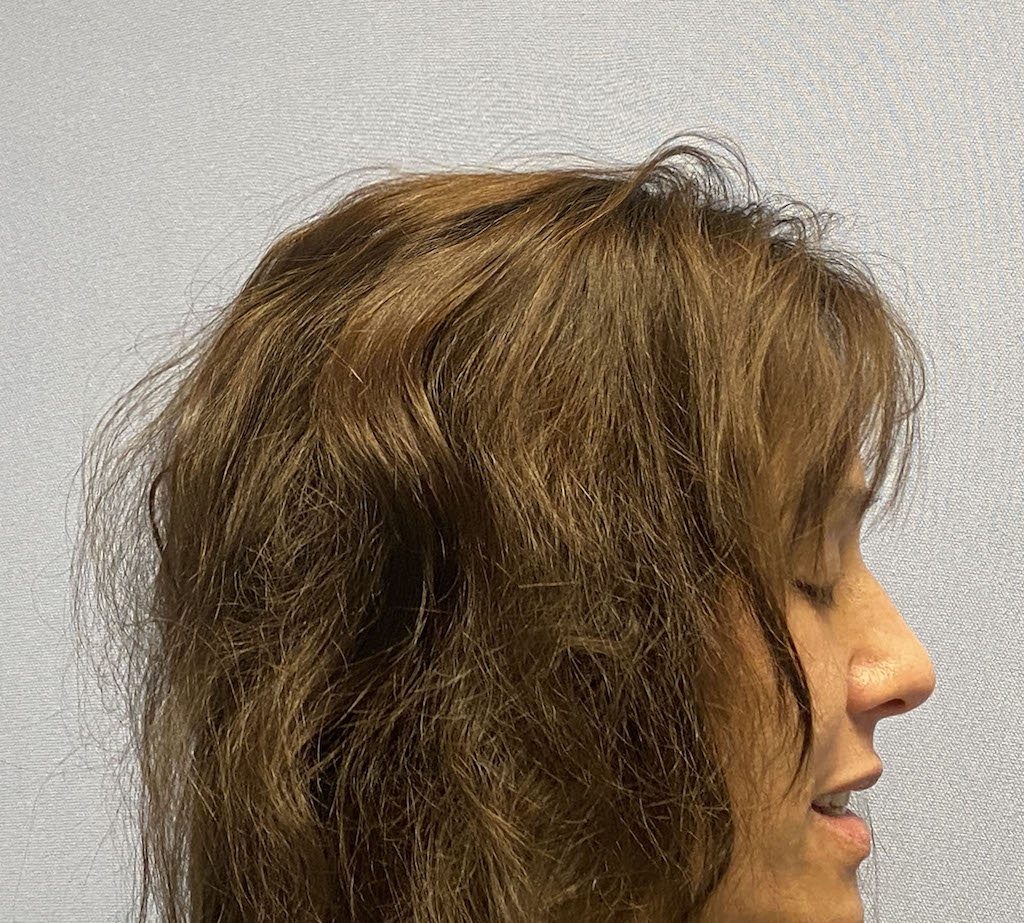

Patient 51

Desire for taller and rounder head shape.

Two stage custom skull implant augmentation technique.

Desire for taller and rounder head shape.

Two stage custom skull implant augmentation technique.